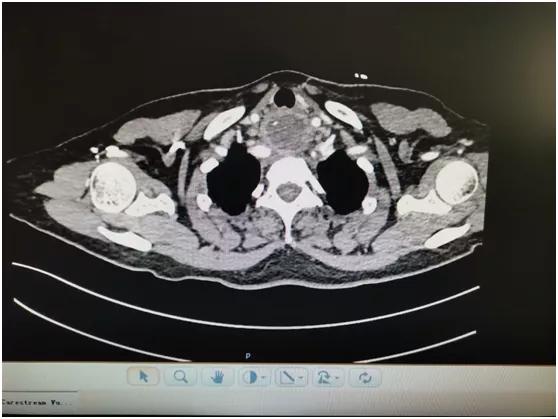

近日,患者来我院耳鼻喉科就诊,主任医师李学昌查看后嘱其立即行胸部 CT 平扫+强化,结果显示:食管上端见囊性影,大约 3.2 cm×4 cm,内见斜行条形高密度影及液气平面,增强见环形强化,此脓肿前位于气管后方,后至颈椎前方,上位于食管上端,锁骨水平,下至上纵膈。

李学昌、陈尧向患者及家属解释患者目前病情危急,感染加重随时可能出现纵膈感染甚至感染性休克,需要急诊手术取鸡骨,并解释手术方式及可能出现损伤喉返神经引起声嘶、损伤大动脉引起大出血等严重并发症,患者及家属表示理解,给予安排手术。手术由头颈外科手术经验丰富的陈尧主刀,于胸骨上窝一横指处颈部正中作横行切口,分离出左侧喉返神经,分离出甲状腺下级,分离出气管后壁、食管前壁,仍未发现脓肿,考虑可能位于食管后壁,继续探查食管周围,于食管后方发现脓肿,抽出约 15 ml 黄绿色脓液,臭鸡蛋味,于脓肿腔内发现约 2 cm 长鸡骨一块(如图)。冲洗脓腔,放置引流管,关闭术腔。